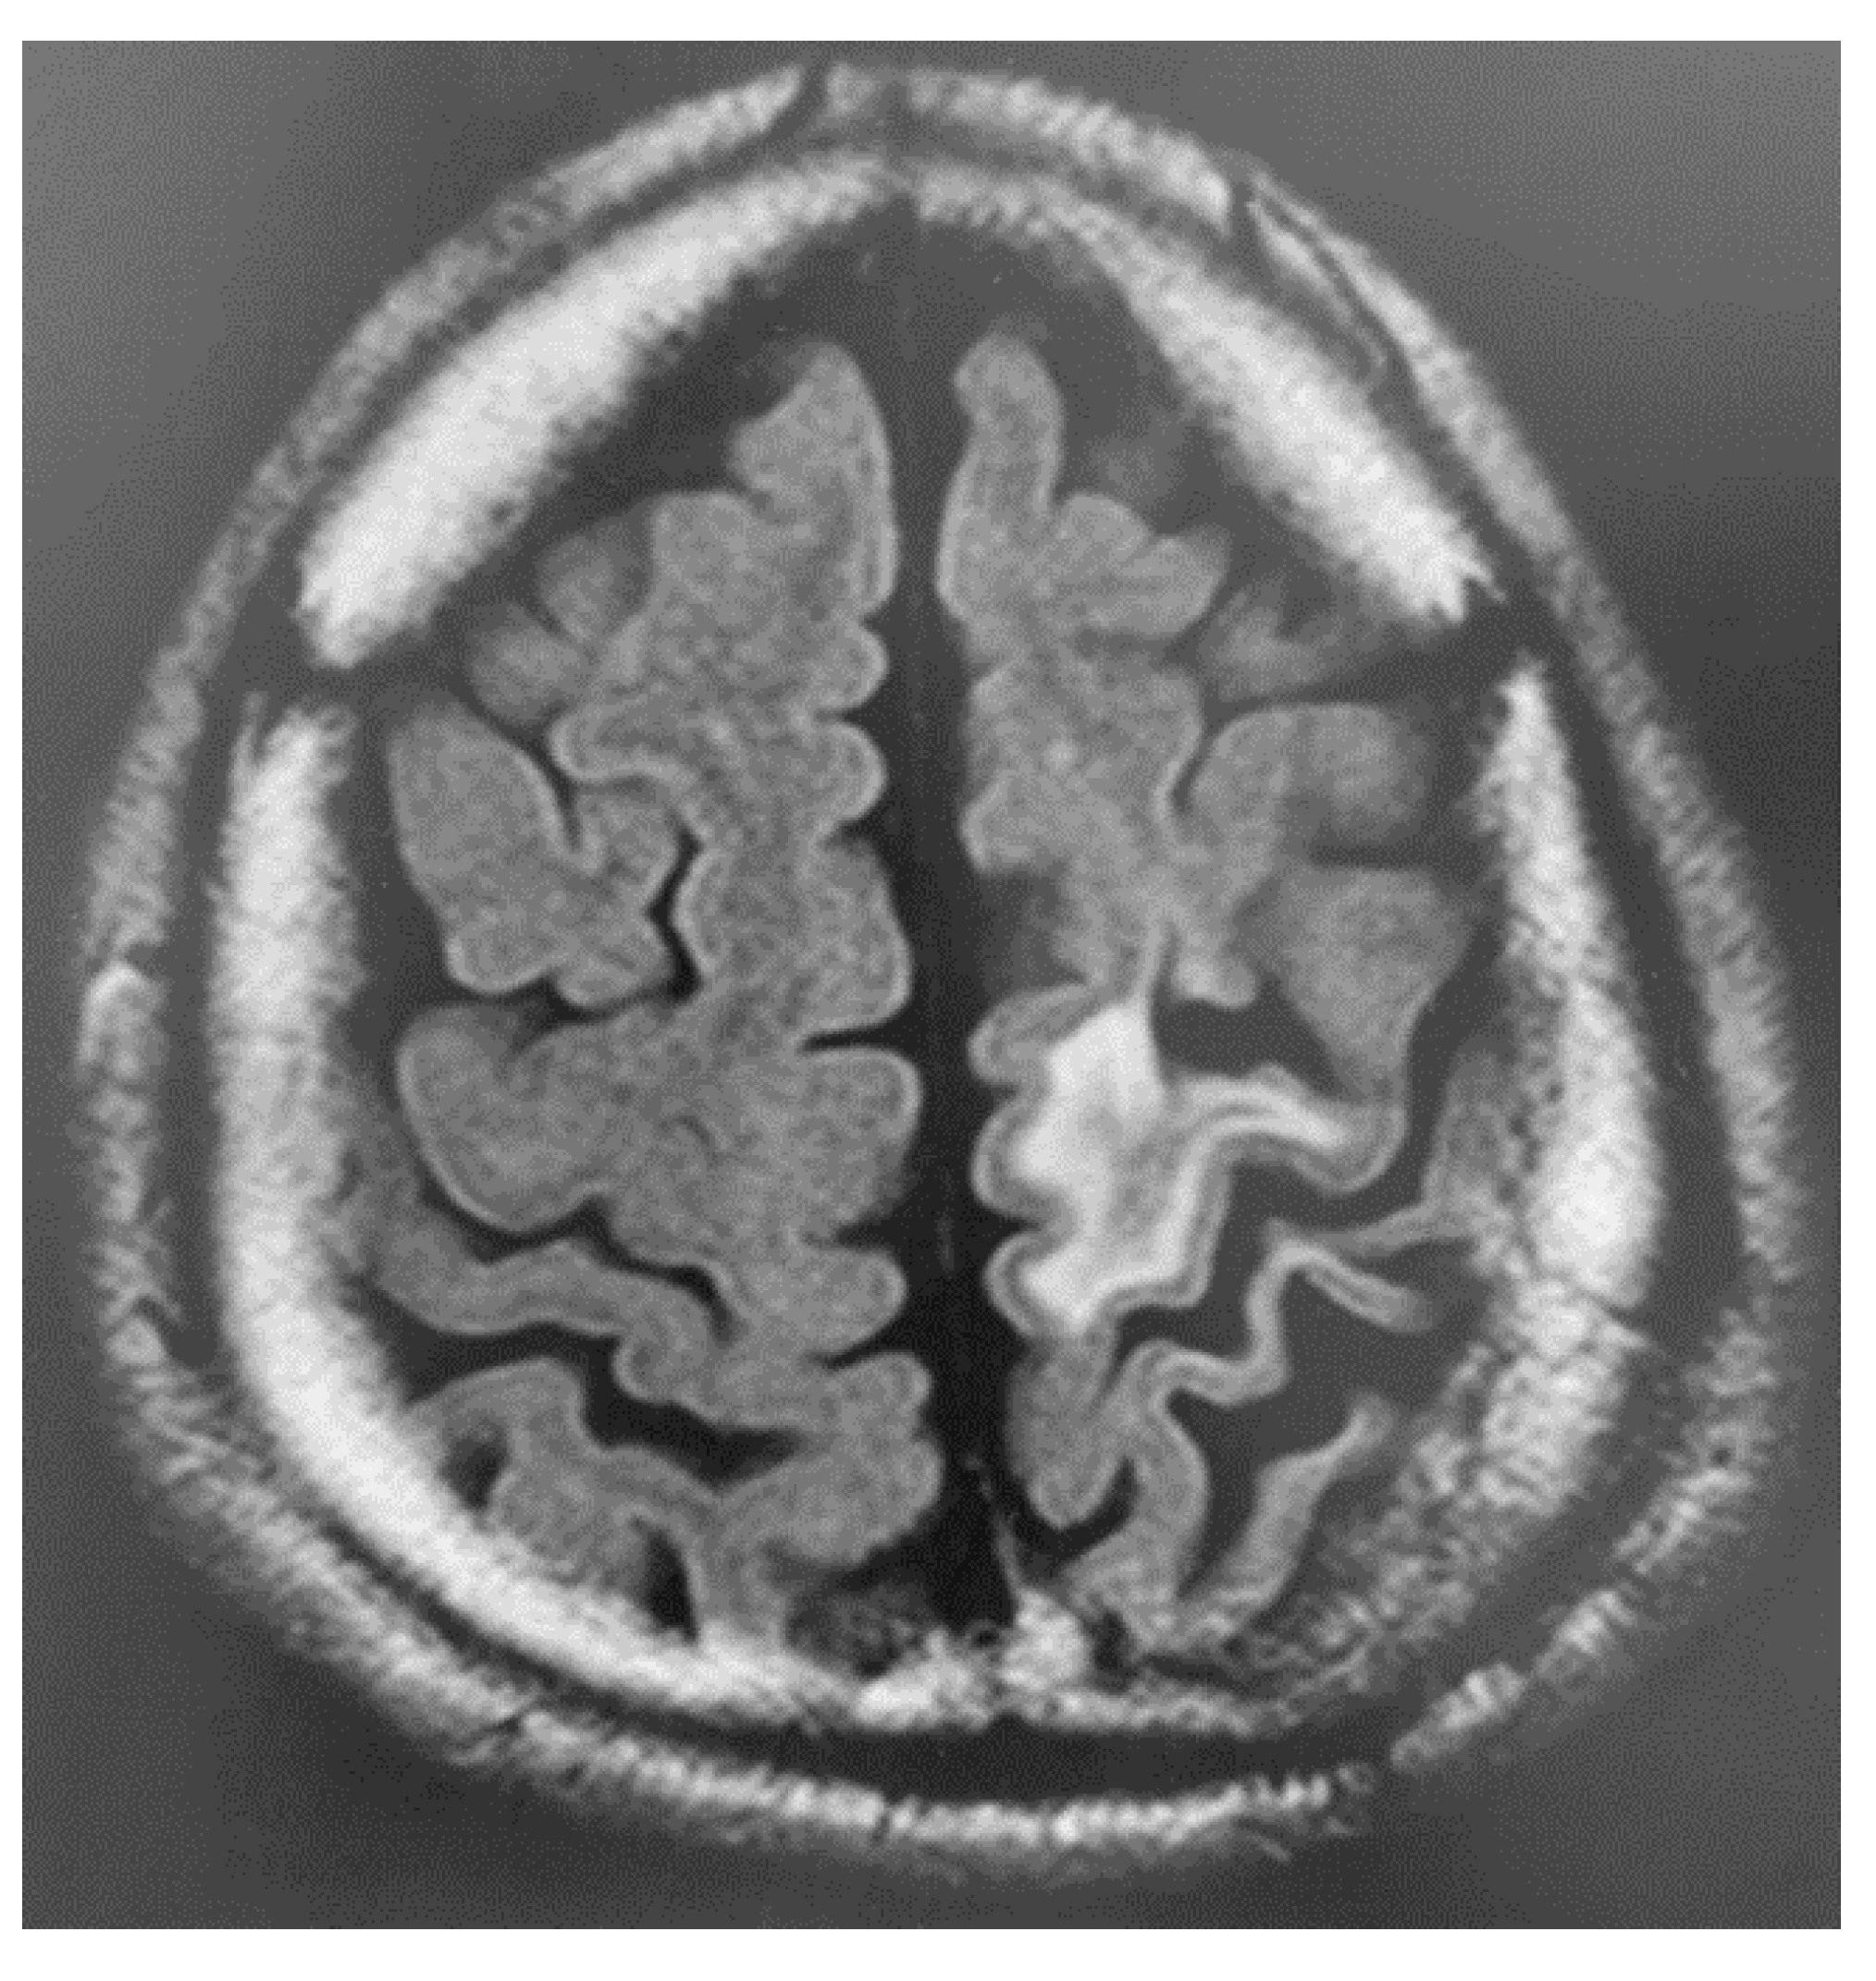

During the medical examination, the patient expressed sincere remorse over the alcohol-related problems and desired to seek solutions. Accordingly, we started a detailed examination for higher brain dysfunction and requested a psychiatric assessment for specialized treatment of alcohol dependence/abuse. The patient was diagnosed with higher brain dysfunction based on social behavioral deficits in daily life and memory deficits confirmed by neuropsychological testing. Figure 2 and Figure 3 show the results of brain imaging performed on his first visit to our department. MRI revealed cerebral atrophy in the region from the left frontal lobe to the parietal lobe; furthermore, SPECT (Single Photon Emission Computed Tomography) confirmed decreased blood flow in the region from the left frontal lobe to the parietal lobe, as well as bilaterally decreased blood flow in the basal ganglia (near the thalamus) and brain stem (near the midbrain). Table 2 shows the results and timeline of the neuropsychological tests performed. His intelligence was consistently at the lower limit of normal from the examination 1 year after the injury to the most recent examination 23 years after injury, and his memory impairment was consistently conspicuous at all examination time points. Other tests showed no apparent decline. He consumed alcohol while receiving treatment for alcoholism in an alcoholic rehabilitation facility, after stealing alcoholic drinks from a convenience store. Currently, his alcohol impulse control disorder persists with repeated episodes of alcohol consumption and difficult behavior after sneaking away from home. At the age of 38 years, he was caught shoplifting at a home improvement store while sober and is currently on trial for impulsive behavior regardless of alcohol consumption. He has been arrested many times, with his mother expressing her frustration saying, “It would have been better if he died in the car accident if he was going to cause so much trouble to others”.

Figure 2. Brain MRI scan of Patient 2 (fluid-attenuated inversion recovery) shows high signal intensity and atrophy in the left frontal and parietal lobes, suggesting old brain injury.